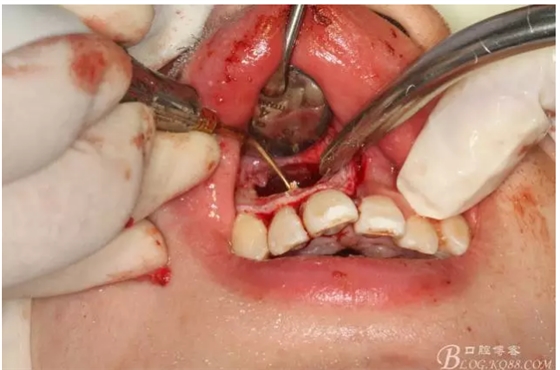

圖3.依缺損部位為中心,逐漸去骨,完整暴露出囊壁。